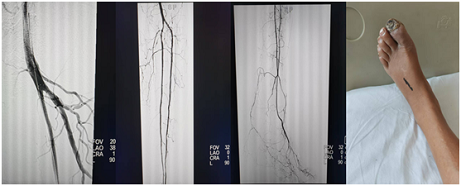

- 2025-08-07▪ 打破专业壁垒,提供精准护理︱郑州大学五附院护理部顺利开展下肢动脉硬化闭塞症患者的护理多学科联合会诊(MDT)